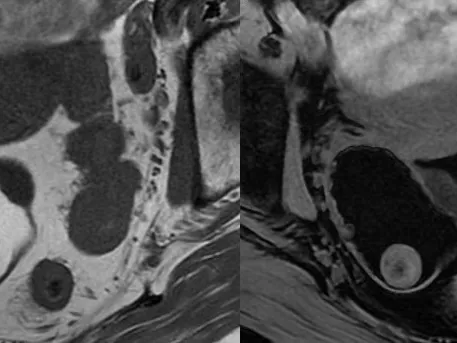

Part 1 covers: Female Pelvic Anatomy, MRI protocols, and Reading Tips / Congenital Uterine Anomalies / MRI of Benign Uterus / MRI of Uterine Sarcomas / MRI of Endometrial Cancer / MRI of Cervical Cancer

Part 2 will cover: MRI Adnexal Lesion Characterisation / Ovarian Cancer Staging / Chronic Pelvic Pain / Endometriosis / Acute Pelvic Pain / Imaging of Mesh Complications Visit Female Pelvis MRI Fellowship Part 2